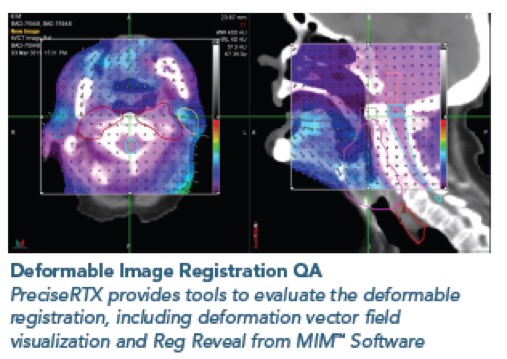

PreciseRTX™ - Για την ασφαλή χορήγηση θεραπείας σε περίπτωση επανακτινοβόλησης

Στην περίπτωση επανακτινοβόλησης, το σύστημα PrecisionRTX επιτρέπει την εισαγωγή των δεδομένων από προηγούμενες θεραπείες και την ενσωμάτωση τους στο νέο πλάνο ακτινοθεραπείας.

Στην περίπτωση επανακτινοβόλησης, το σύστημα PrecisionRTX επιτρέπει την εισαγωγή των δεδομένων από προηγούμενες θεραπείες και την ενσωμάτωση τους στο νέο πλάνο ακτινοθεραπείας.

Σε συνδυασμό με την ικανότητα του συστήματος TomoTherapy να δημιουργεί σύμμορφα πλάνα αποφεύγοντας κρίσιμα όργανα, το σύστημα PreciseRTX™ δίνει την δυνατότητα στους ακτινοθεραπευτές Ιατρούς να προσφέρουν ασφαλείς θεραπείες στους ασθενείς που έχουν λάβει προηγούμενες θεραπείες με ακτινοβολία

PreciseRTX

- Επιτρέπει την εισαγωγή προηγούμενων πλάνων θεραπείας ασθενών από οποιαδήποτε άλλο σύστημα.

- Αποτελεί μια ενσωματωμένη λύση στο σύστημα σχεδιασμού θεραπείας Precision η οποία εξαλείφει την ανάγκη μεταφοράς δεδομένων μεταξύ συστημάτων διαφορετικών κατασκευαστών.

- Ευθυγραμμίζει αυτόματα τα απεικονιστικά δεδομένα και τα δεδομένα των πλάνων θεραπείας (σχεδιασμένες δομές και δοσιμετρικές κατανομές) προηγούμενων θεραπειών με τις νέες εικόνες αξονικής τομογραφίας λαμβάνοντας υπόψη μεταβολές στην ανατομία του ασθενούς (Deformable registration)

- Αθροίζει τις κατανομές δόσης των προηγούμενων θεραπειών με την κατανομή δόσης του νέου πλάνου θεραπείας.

- Περιλαμβάνει εργαλεία αξιολόγησης των συνολικών και των επιμέρους δοσιμετρικών κατανομών.